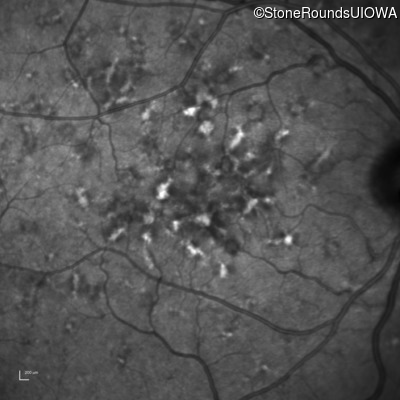

Age at visit: 49 years

This 49 year old man was first told he had a fundus abnormality on a routine eye exam at age 34. Ten years later he noticed some distortion just superior to fixation.

Pattern Dystrophy PRPH2 Gln239Stop CAG>TAG   AD